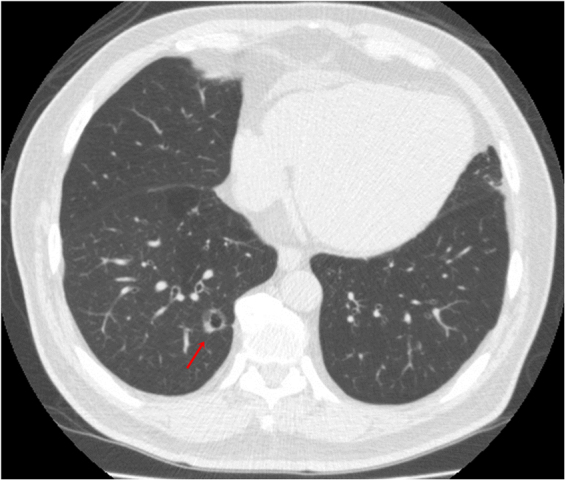

All scans were performed with a 16-slice CT (Somatom Sensation 16, Siemens Healthcare, Erlangen, Germany), a 64-slice CT (Aquilion 64; Toshiba Medical Systems), and 256-slice CT (Revolution CT, GE Healthcare, Milwaukee, USA) from the lung apex to the base without contrast enhancement. Images were reconstructed with a section thickness of 1–2.5 mm and displayed at a lung window width of 1600 HU, window level of −600 HU, and a mediastinal window width of 350 HU, with a window level of 35 HU. CT characteristics were retrospectively reviewed and analyzed by 2 experienced thoracic radiologists (FZW and MTW), with 9 and 30 years of experience in thoracic radiology, respectively. The imaging features for each nodule with pathologically proof were analyzed according to the following parameters: (1) lesion size, (2) solid part in a mediastinal window, (3) SSN subclassification into pure GGN, heterogeneous GGN (partly consolidated on lung windows), and part-solid nodules (with a mediastinal window solid component) according to the previous prospective study proposed by Kakinuma et al., (4) air-bronchogram (an example in Fig. 2), (5) abnormal cystic-like airspace (an example in Fig. 3), (6) Lung-RADS report of all SSNs, and (7) the attenuation values of pure and heterogeneous GGNs. Maximal diameters of the nodular lesion with solid components (in the maximal diameter when viewing using a mediastinal window setting) were measured on CT on axial images. The mean, minimum, and maximum CT attenuation expressed in HU was measured by placing a region of interest (ROI) of 15 mm2 on the lesion using a GE Advantage Server 2.0 (GE Healthcare). In addition, to avoid placing the ROI box in or near the blood vessels could reduce the measurement errors (examples in Figs 4 and 5).

Figure 2.

An example of subsolid nodule with an air bronchogram sign according to the SSN subclassification. A 61-year-old woman had a 1.4 cm part-solid nodule in RUL. The (A) coronal and (B) oblique images showed an internal air bronchogram inside the lesion. The patient underwent video-thoracoscopic wedge resection of RUL. Further pathologic report demonstrated invasive pulmonary adenocarcinoma in RUL, Stage 1. Abbreviations: SSN = subsolid nodule; RUL = right upper lobe.